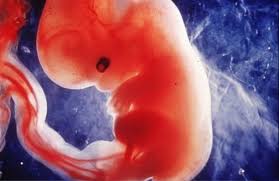

Erreur de sexe d abord garcon devient fille. Il est donc difficile de connaitre le sexe du bébé à la première échographie. La fille, à être sage, soumise, dans le désir de l'autre.